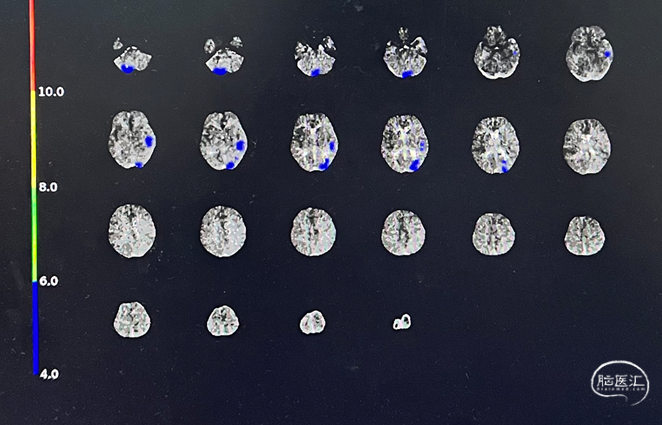

本例患者是左侧大脑前动脉A2段动脉瘤,形态不规则,合并载瘤动脉狭窄,采用血流导向装置植入治疗后获得较好的影像学结果。